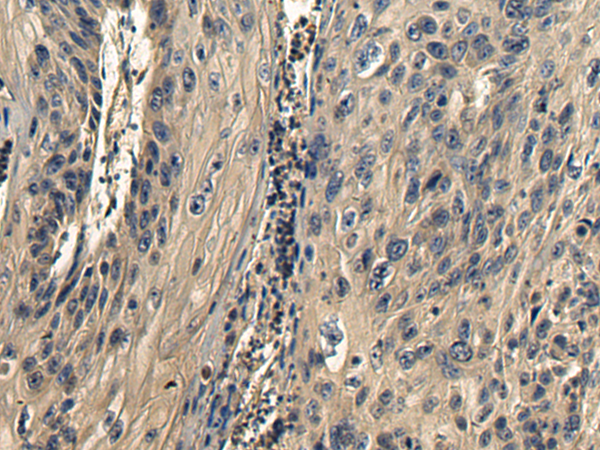

分类: 科研抗体货号: P10423别名: SAV; WW45; WWP4应用: WB,IHC反应种属: Human, Mouse, Rat